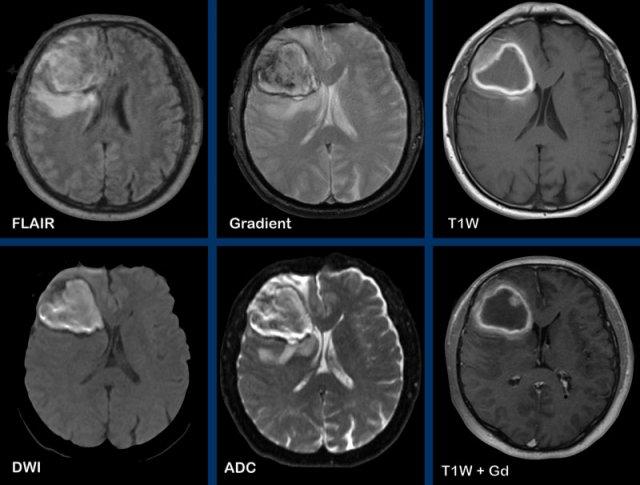

Các hình ảnh này của bệnh nhân nam 47 tuổi, nhập viện với các triệu chứng đau đầu, nôn mửa và liệt nửa người bên phải.

Hình ảnh

Ghi nhận một tổn thương ngấm thuốc dạng vòng viền tại hạch nền bên trái.

Lưu ý các cấu trúc ngấm thuốc nằm dọc theo bờ trong của vòng viền ngấm thuốc.

Không có hạn chế khuếch tán, điều này làm cho chẩn đoán áp xe não ít có khả năng xảy ra.

Đây là trường hợp GBM (u nguyên bào thần kinh đệm) đã được xác nhận bằng giải phẫu bệnh.

Các hình ảnh này của bệnh nhân 55 tuổi, nhập viện với các triệu chứng đau đầu và mất ngôn ngữ.

Hãy quan sát các hình ảnh trước rồi tiếp tục đọc.

- Các dấu hiệu hình ảnh là gì?

- Chẩn đoán có khả năng nhất là gì?

Ghi nhận một tổn thương vùng trán-thái dương trái, tăng tín hiệu trên chuỗi xung T2W, với vòng viền ngấm thuốc dày và không đều.

Tổn thương lan dọc theo và xâm lấn vào chất trắng theo hướng bó móc và các sợi chữ U.

Trung tâm tổn thương không có hạn chế khuếch tán và không ngấm thuốc, nhiều khả năng là vùng hoại tử.

Chẩn đoán có khả năng nhất là GBM (u nguyên bào thần kinh đệm).

Các u thần kinh đệm có nguồn gốc từ tế bào thần kinh đệm trong hệ thần kinh trung ương và là các u xâm lấn.

GBM là u não nguyên phát ác tính nhất.

Chúng xâm lấn lan tỏa dọc theo các bó chất trắng, ví dụ như thể chai.